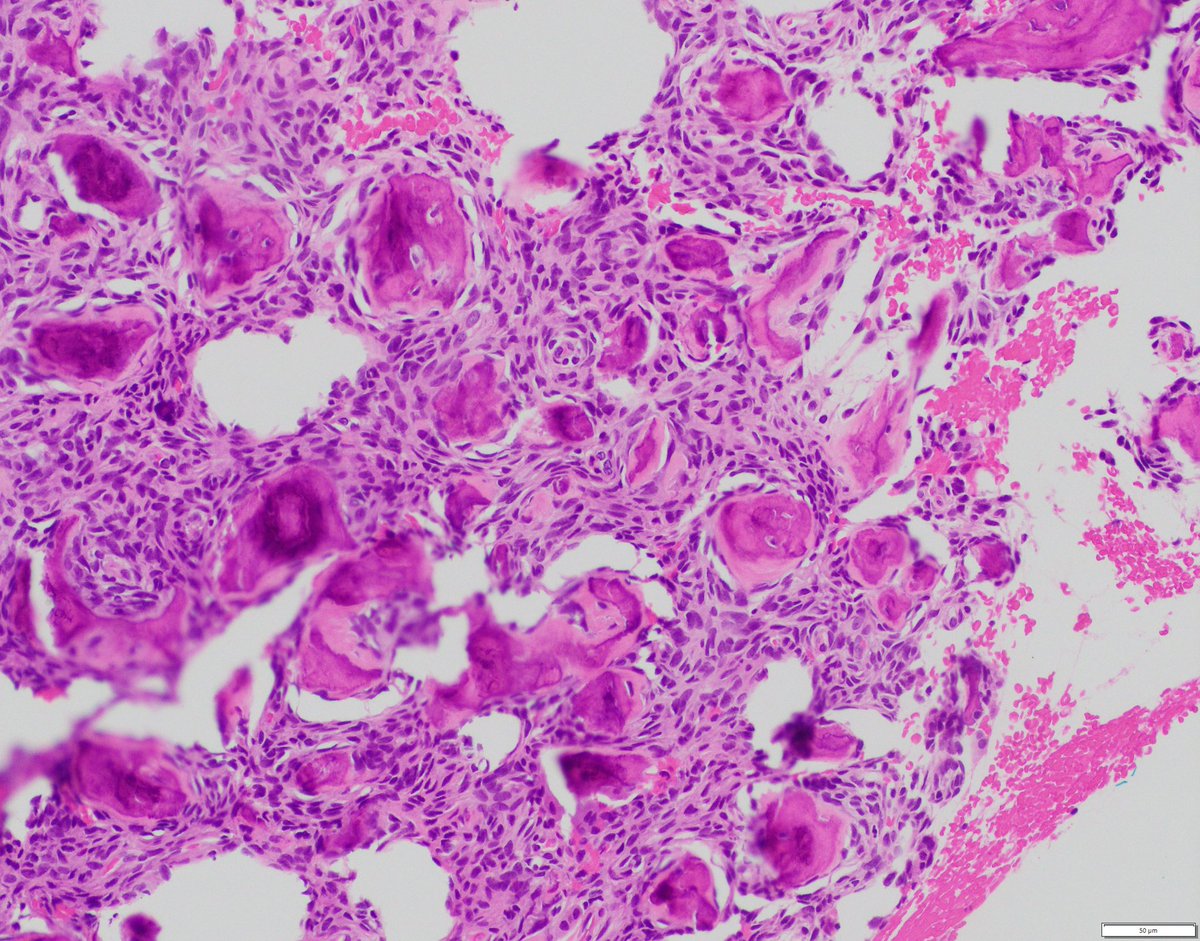

Polypoid vaginal mass from a young girl. Your diagnosis? More pics https://t.co/DaWIpwic4N Immunostains 🔬 https://t.co/EAiO8vGSkt Answer ✅ https://t.co/czXR6VkiRs #BSTpath #pathologists #pathology #pathTwitter #gynpath #pedipath